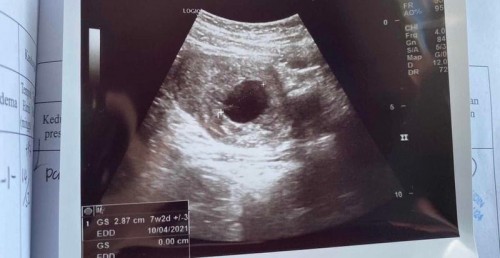

Mempercepatkan keguguran natural (kandungan kantung)

Harini bleeding kali 2 .. Semalam dh pergi hospital tp doktor suggest utk keguguran natural , if ada pendarahan teruk baru pergi hospital.. atau selepas 2 minggu tiada kantung keluar baru doktor bg buat D&C.. Masalahnya harini dah start sakit macam segugut tapi tak keluar darah banyak pun.. Sesiapa tahu tips untuk mempercepatkan keguguran ?? #mengandungkantungtanpajanin

3bulan sis. Alhamdulilah dh selamat keguguran natural semasa Di Hospital Kajang doktor pakar bagi ubat induce. Selepas beberapa jam baru fully miscarriage.